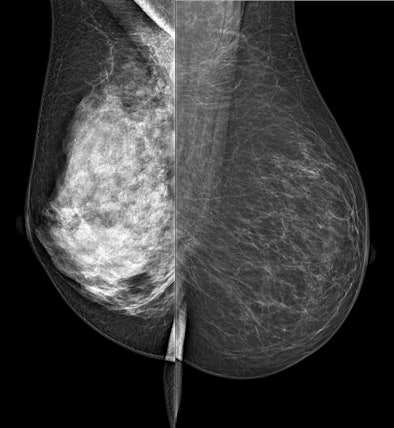

| Spectral mammography images: left is high-density breast tissue; right is low density. Image courtesy of AAPM |

Spectral mammography compared to standard mammography is like color television compared to black and white, Molloi said. Spectral mammography allows the image to be viewed at two different energy levels instead of just one, helping to quantify the density of a woman's breasts and, in turn, her relative risk.

The results showed that spectral mammography could measure volumetric breast density in a screening exam with better than 2% accuracy, Molloi said. The technology also reduced the standard mammography radiation dose by 50%.